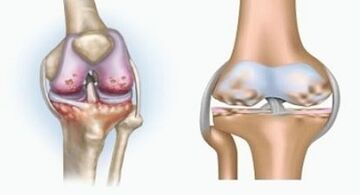

Both pathologies affect the joints, but differ in the nature of the change.

Arthritis is an inflammation of the connective tissue - a synovial membrane that contains many vessels and provides lymph flow.The process of inflammation leads to a violation of articular tissue nutrition, as a result of the production of articular lubrication - synovial fluid is limited.

Arthrosis is a degenerative-dystrophic process related to the destruction of cartilage tissue.The cartilage is gradually destroyed, dry, the distance between the joints decreases, which is the cause of pain.In severe form, destruction affects the bone.They become more porous, lose their density, become fragile.